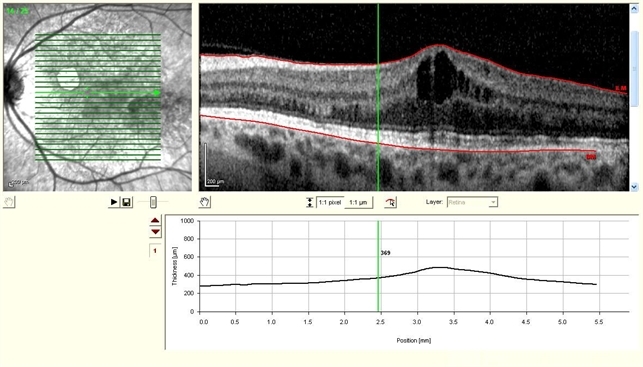

- optical coherence tomography (OCT), rubella retinopathy, Spectralis

Optical coherence tomography system

spectralis - Description

- 48-year-old, deaf female, complains of blurry vision, mother had Rubella when she was pregnant.